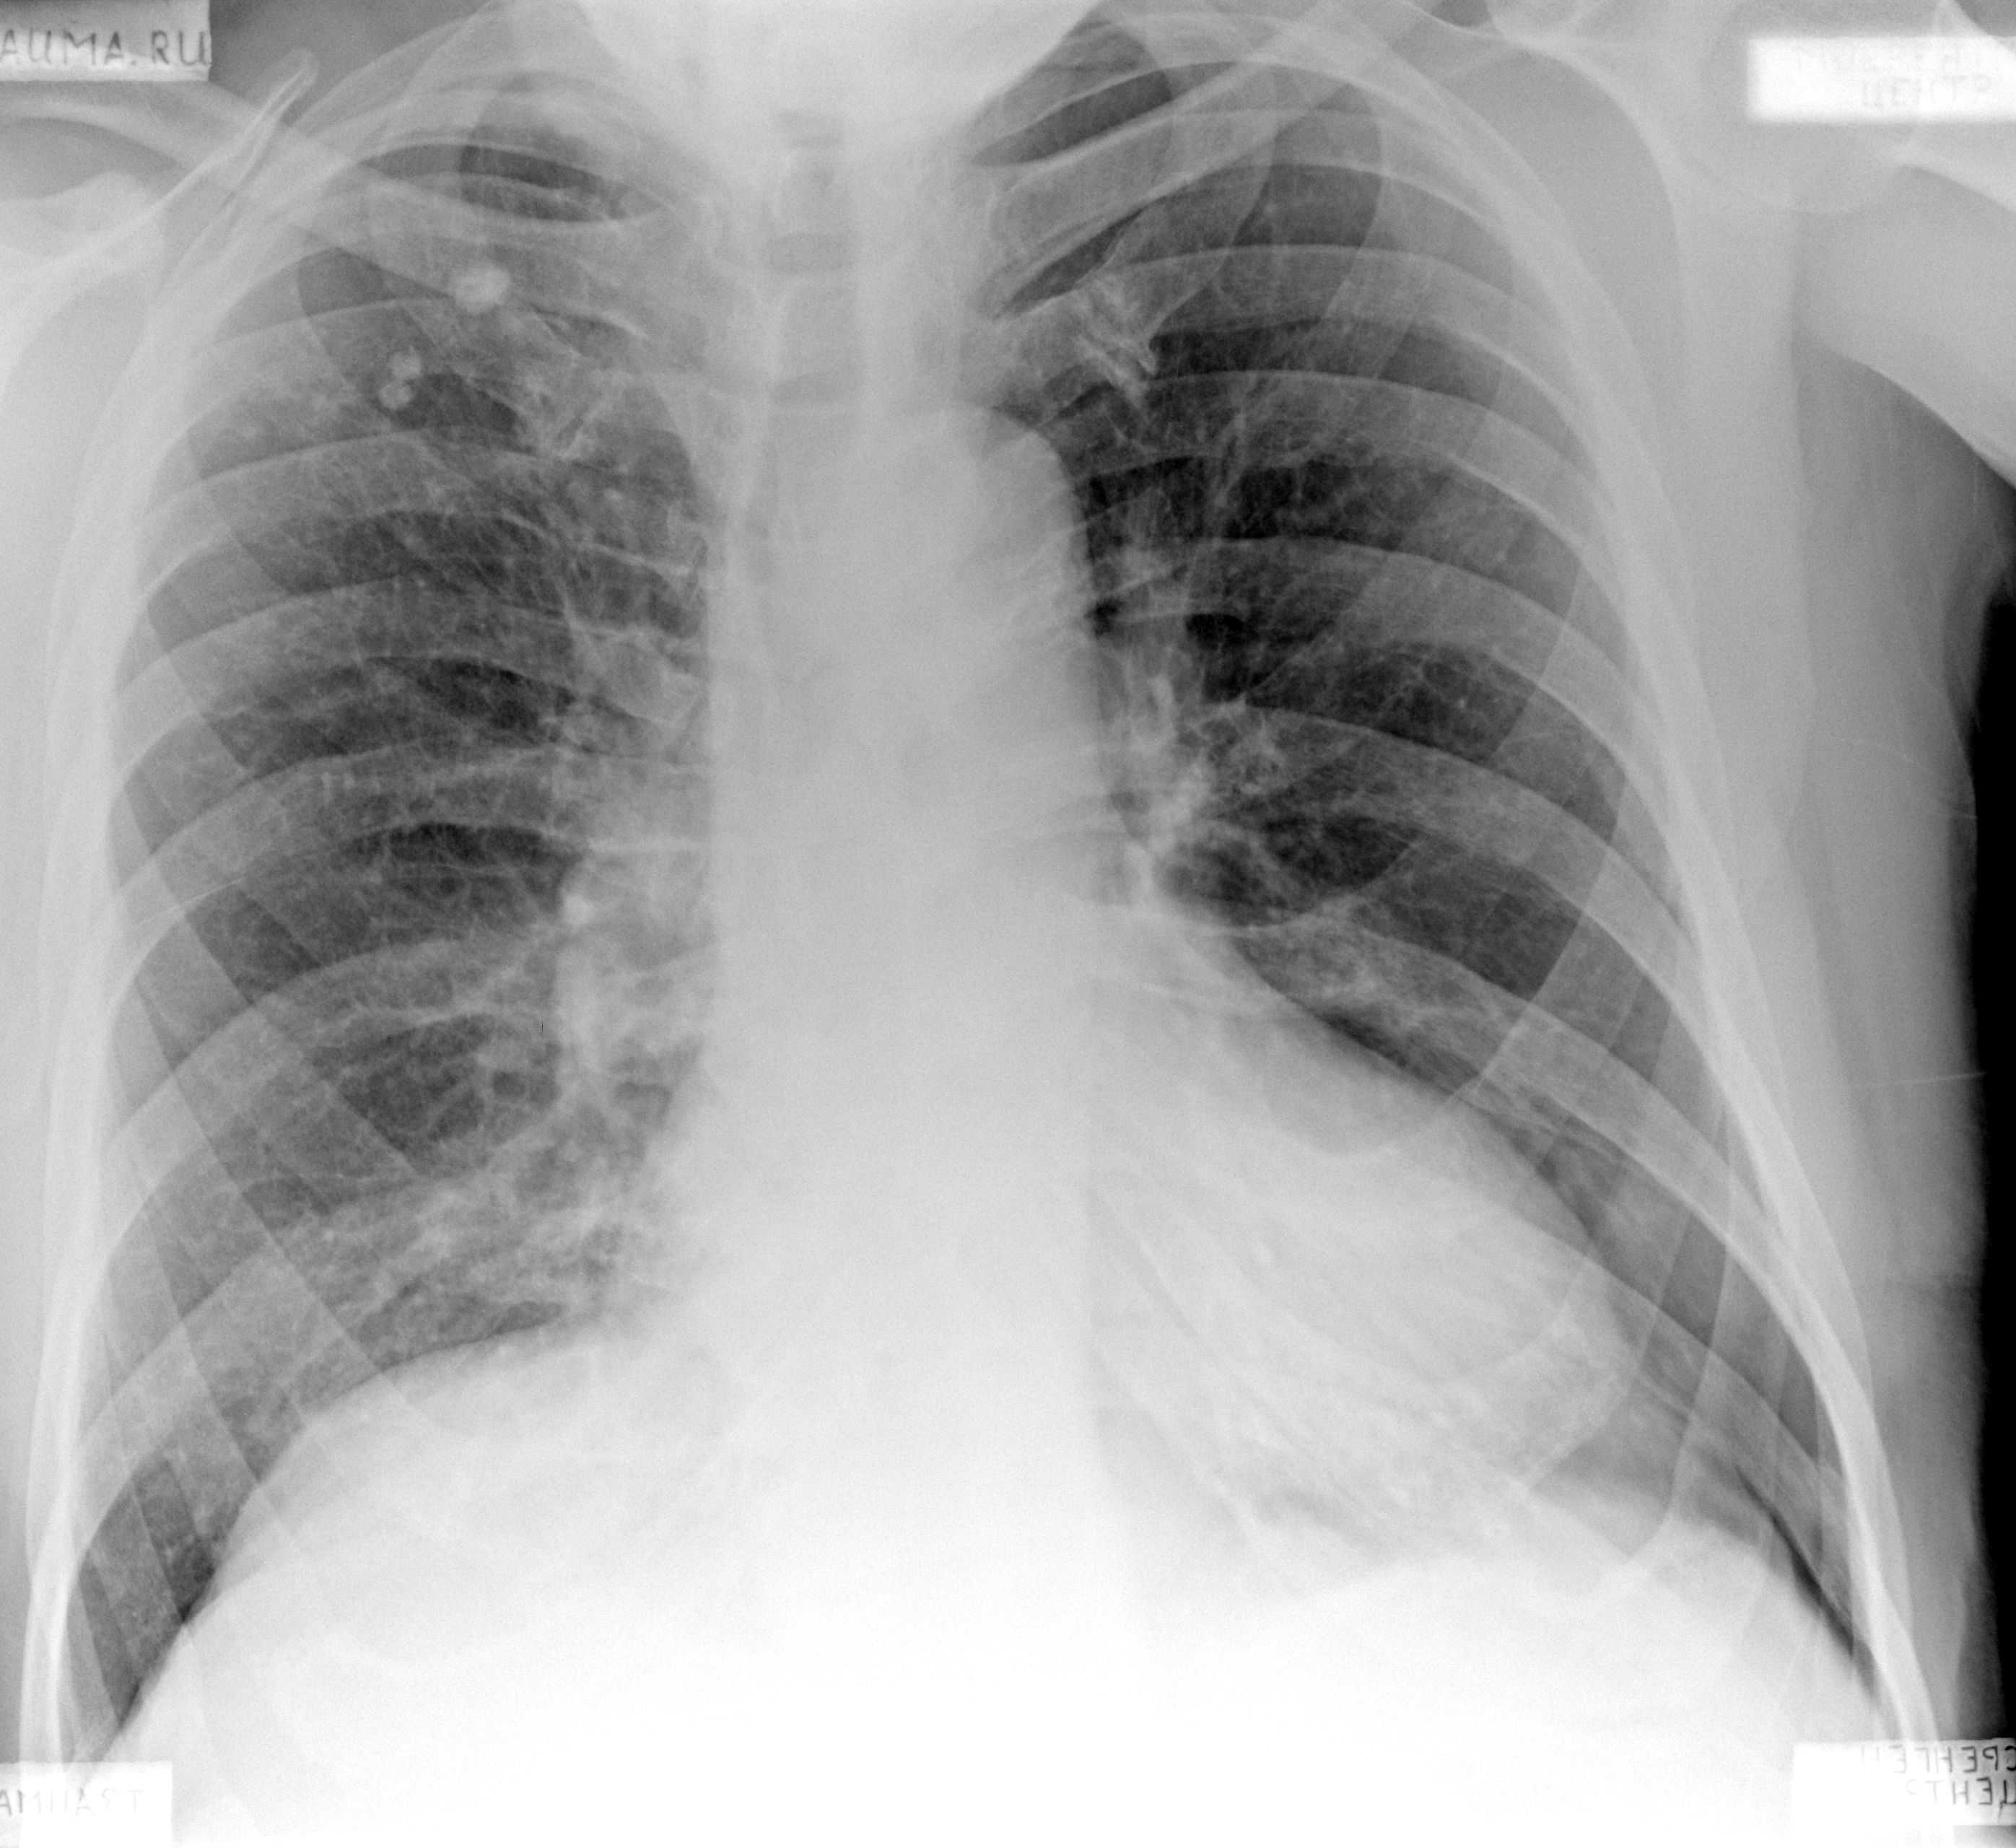

Изучение дозы излучения при рентгеновских исследованиях: визуализация